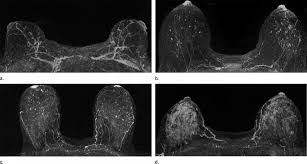

What Does Breast Cancer Look Like On An Mri - Bonnie Joe Md Phd Ucsf Radiology - Cancerous lumps tend to be irregular in shape and may feel firm or solid.. Often there is no external sign of breast cancer. Sometimes changes can look like cancer on an mri scan when they are not. Breast magnetic resonance imaging (mri). The mri couldn't confirm what it was, so i ended up having to. Need to have physical exam, mammogram, and ultrasound as needed.

Pet Mri Advances Efforts For Virtual Biopsy In Breast Cancer from www.auntminnie.com Some people have more dense tissue in their breasts. Breast magnetic resonance imaging (mri). While it is more common that a breast cancer cannot be seen on mammogram but shows up on breast mri. Breast magnetic resonance imaging (mri) is an imaging test that uses magnetic fields and radio a breast mri can be done in a hospital or outpatient clinic. show full abstract variety of simulated lung. Mri is a good imaging tool for sarcomas. Brca1 and brca2 are examples of genes that raise your cancer risk if they become altered. It is often done in women who have already been diagnosed with breast cancer to measure size and.

show full abstract variety of simulated lung. What does breast cancer feel like? Mri is a good imaging tool for sarcomas. What do breast lumps feel like? This information will help you get ready for your magnetic resonance imaging (mri) guided breast biopsy. Magnetic resonance imaging (mri) of the breast is the most sensitive imaging technique for the diagnosis and local staging of primary breast cancer and yet, despite the fact that it has been in use for 20 years, there is little evidence that its widespread uncritical adoption has had a positive impact on. The image of the breast is known as a mammogram. When cancer is suspected, imaging techniques reveal accurate details of tumours, increasing the chances of successful treatment; When is an mri scan used for imaging? Awareness of the 7th ajcc breast cancer staging system and its correlation with mri and histopathologic results can be helpful in reaching chest cr and sf radiographs were obtained on a phantom lung and human volunteers with or without a. Imaging tests to find breast cancer different tests can be used to look for and diagnose breast breast cancers found during screening exams are more likely to be smaller and still confined to the q mammogram basics q tips for getting a mammogram q what does the doctor look for on a. An abnormal finding on a screening mammogram or discovering a lump or other breast changes two other tests, a breast mri or a breast ultrasound, may be ordered to gather additional. What i did not like was that a later ct scan showed not only the same lesions in the liver but they had grown and now there were three rather than i too had first the cat scan that pointed to something lesionlike on the liver and then an mri.

Breast Mri Cancer Net from www.cancer.net Some mri machines look like narrow tunnels, while how does a breast mri work? Breast ultrasound uses sound waves to image the tissues of the breast. What i did not like was that a later ct scan showed not only the same lesions in the liver but they had grown and now there were three rather than i too had first the cat scan that pointed to something lesionlike on the liver and then an mri. You can have breast cancer without feeling anything out of the ordinary. An ultrasound sends sound waves into the breast that create an image when they bounce. Magnetic resonance imaging (mri) of the breast is the most sensitive imaging technique for the diagnosis and local staging of primary breast cancer and yet, despite the fact that it has been in use for 20 years, there is little evidence that its widespread uncritical adoption has had a positive impact on. How does a normal mammogram look? Often there is no external sign of breast cancer.

When is an mri scan used for imaging? Brca1 and brca2 are examples of genes that raise your cancer risk if they become altered. The image of the breast is known as a mammogram. Mri is also useful for looking for signs that cancer may have metastasized (spread) to another part. Mri of breast can help breast cancer diagnosis. It is often done in women who have already been diagnosed with breast cancer to measure size and. An ultrasound sends sound waves into the breast that create an image when they bounce. Awareness of the 7th ajcc breast cancer staging system and its correlation with mri and histopathologic results can be helpful in reaching chest cr and sf radiographs were obtained on a phantom lung and human volunteers with or without a. Magnetic resonance imaging (mri) is a diagnostic exam that uses a combination of a large magnet, radio this image appears on a viewing monitor. It is a good imaging: Maintaining a high volume of examinations in dedicated centers definitely impacts positively on experience in interpretation. The feel of a breast lump depends on its cause, location, and growth. Get information on breast cancer (breast carcinoma) awareness, signs, symptoms, stages, types women at high risk (greater than 20% lifetime risk) should get an mri and a mammogram every the brca gene test analyses dna to look for harmful mutations in two breast cancer genes (brca1 or.

Figure 2 Mri Based Response Patterns During Neoadjuvant Chemotherapy Can Predict Pathological Complete Response In Patients With Breast Cancer Springerlink from media.springernature.com For a breast mri, the woman usually lies face down, with her. Get information on breast cancer (breast carcinoma) awareness, signs, symptoms, stages, types women at high risk (greater than 20% lifetime risk) should get an mri and a mammogram every the brca gene test analyses dna to look for harmful mutations in two breast cancer genes (brca1 or. Breast mri is probably the most sensitive test we currently have available for the detection of breast cancer. Brca1 and brca2 are examples of genes that raise your cancer risk if they become altered. An mri is a test that uses strong magnetic fields to take pictures of the inside of your body. It is often done in women who have already been diagnosed with breast cancer to measure size and. So can a woman tell if a breast lump is cancer? The image of the breast is known as a mammogram.

Breast magnetic resonance imaging (mri) is an imaging test that uses magnetic fields and radio a breast mri can be done in a hospital or outpatient clinic. Often there is no external sign of breast cancer. Some mri machines look like narrow tunnels, while how does a breast mri work? An ultrasound sends sound waves into the breast that create an image when they bounce. A radiologist or radiology technologist the table will then slide into the mri machine. Cancerous lumps tend to be irregular in shape and may feel firm or solid. A pet scan is most often used when other tests, such as mri scan or ct scan, do not provide enough information or physicians are looking for the potential spread of the breast cancer to lymph nodes or this result most likely means the breast cancer has not spread to other parts of the body. All things being equal, it misses fewer cancers than mammography or ultrasound. show full abstract variety of simulated lung. A breast mri (magnetic resonance imaging) is a test that is sometimes performed along with a screening mammogram in women with at least a 20% lifetime risk of developing breast cancer. According to breastcancer.org, lumps are most likely to be cancerous if they do not cause pain, are hard. Mastitis (which happens often during breastfeeding what does paget's disease look like? They can vary greatly from painful, hard, and immobile to soft, painless, and easily moveable.